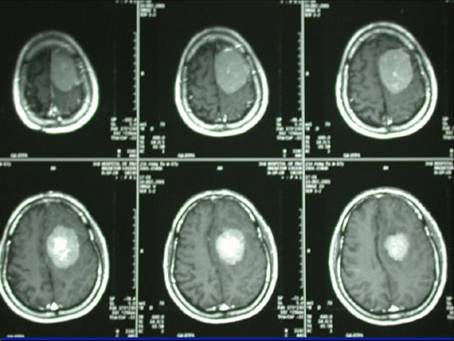

病例1-颅内巨大脑膜瘤

女性,65岁,因右半身轻偏瘫1个月入院。查MRI示:左顶叶窦镰旁脑膜瘤。如下:

术前照片

行显微手术切除肿瘤,simpsonII级全切除。术后照片如下,术后病人偏瘫缓解。

术后照片